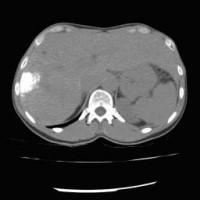

Computertomographische Darstellung eines hepatozellulären Karzinoms (Pfeil) (Bild 1 von 5) Vorwärts »